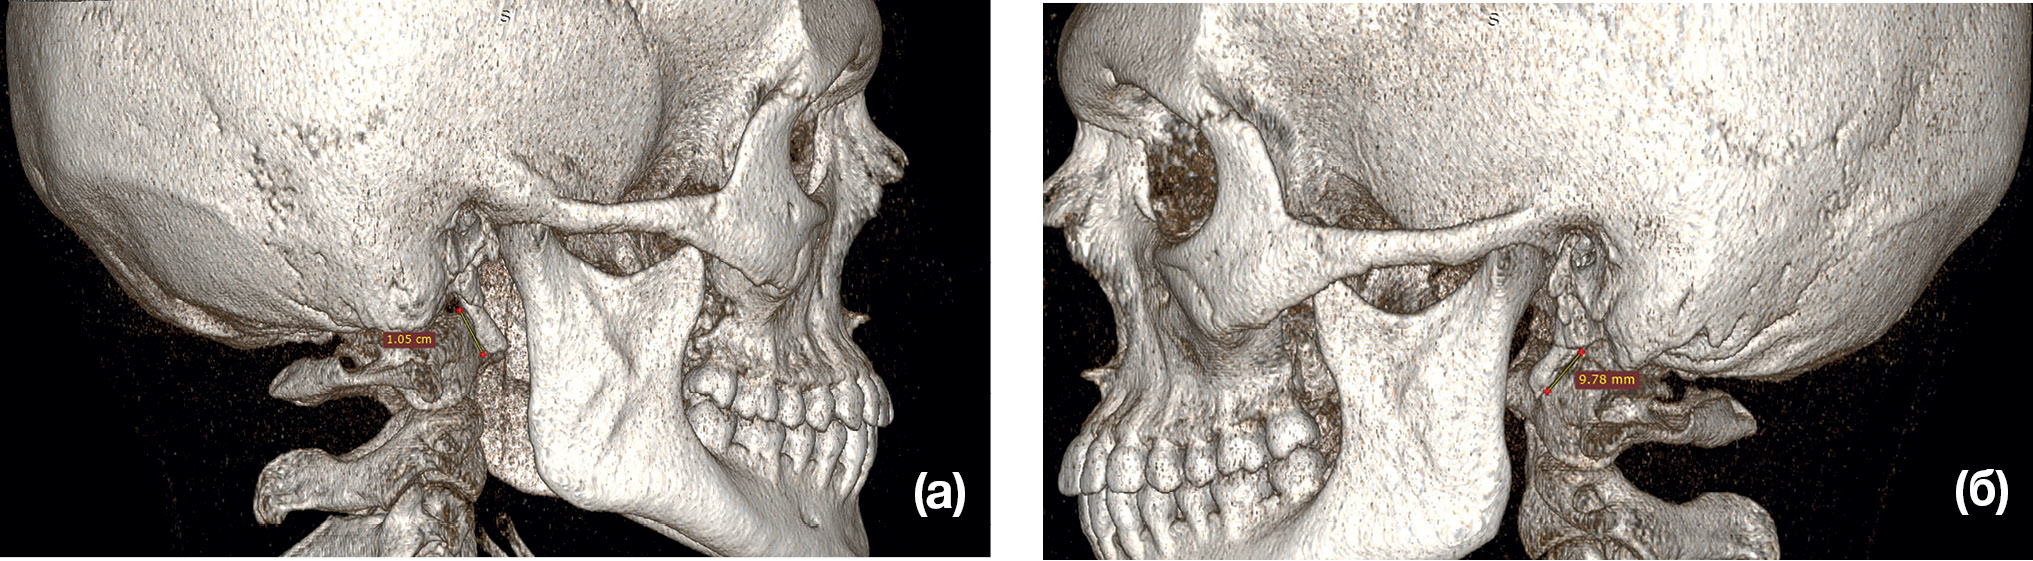

Рис. 1. Компьютерная томография пациентки К., 24 года. Диагноз: Аномалия развития шиловидного отростка височной кости с двух сторон

Примечание. (а) — 3D-реконструкция, вид справа; (б) — 3D-реконструкция, вид слева; (в) — 3D-реконструкция, фас; (г) — корональный срез.